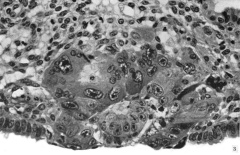

Carnegie Stage 5a-2 Figures

Embryo 8155 original glass slides 4

Amniotic cavity and bilaminar embryonic disc